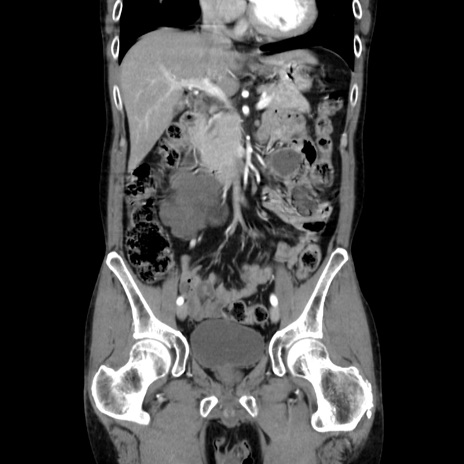

症例37(冠状断像)

【症例】40歳代 男性

【主訴】腹痛

【現病歴】4時間ほど前に電車に乗車中に臍部上より腹痛出現。徐々に増悪し起立困難となり、救急外来受診。生ものは数日食べていない。今朝お雑煮を食べた。

【身体所見】BT 36.8℃、BP 117/84mmHg、HR 91/min、SpO2 97%、苦悶様、腹部:臍上部広範囲圧痛あり、反跳痛±

【データ】WBC 8100、CRP 0.03